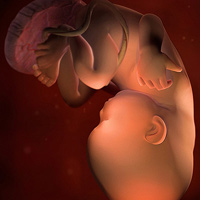

Thời điểm này, lông tơ xuất hiện trên da của bé bắt đầu rụng dần cùng với bã nhờn. Bã nhờn là một chất kem khá dày để bảo vệ da thai nhi trong khi ngâm trong nước ối chín tháng. Bã nhờn và dịch ối kết hợp với nhau tạo thành phân của thai nhi.

Một trong những giai đoạn quan trọng trong sự phát triển của thai nhi là sự hoàn thiện của phổi và hệ hô hấp. Nếu bị đẻ non, trẻ rất dễ mắc phải hội chứng suy hô hấp ngay từ khi mới sinh. Trong trường này là do phổi phát triển không hoàn thiện, thai nhi không có khả năng tự thở mà cần có sự hỗ trợ của máy trợ thở, bình ôxy. Vì vậy, ở tuần 36, hệ thống phổi và hệ hô hấp của bé cũng dần hoàn thiện.

Tóc bé có thể mọc dài đến 5 cm. Các móng tay, móng chân của bé cũng rất dài, vì thể bạn có thể sẽ phải cắt móng tay cho bé khi bé vừa mới chào đời.

Lúc này thành tử cung và thành bụng bạn đang giãn hết cỡ, ngày càng mỏng hơn, đây là cơ hội để bé học hỏi và làm quen với nhịp sinh học ngày và đêm do ánh sáng đã có thể xuyên qua thành bụng chút ít. Thai nhi cũng bắt đầu đùa nghịch với các ngón tay, chân. Thận đã phát triển hoàn thiện và gan cũng đã bắt đầu thực hiện chức năng lọc thải.